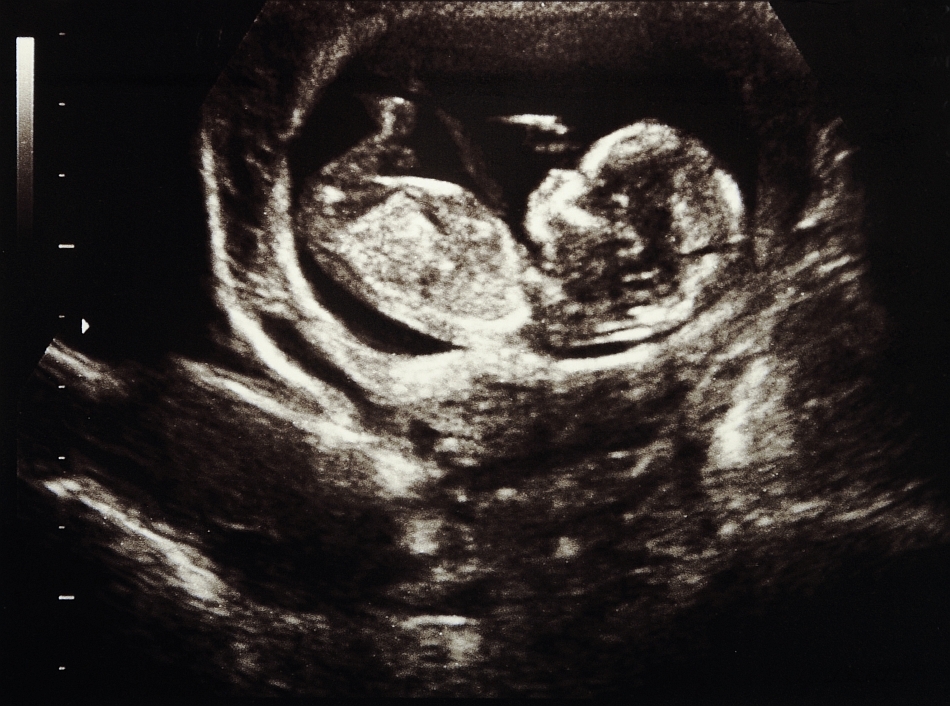

O tehnică similară este folosită în medicină pentru a vizualiza fătul în uterul unei femei – binecunoscuta ecografie.

Lori Marino crede că delfinii ar putea vizualiza o imagine a fătului, deoarece se ştie, din alte studii, că pot converti cu multă acurateţe imaginea acustică dată de ecolocaţie într-o imagine vizuală şi vice versa. La fel cum „poza” de pe ecranul ecografului redă imaginea bebeluşului încă nenăscut, ecolocaţia le-ar putea furniza delfinilor o imagine a fătului.